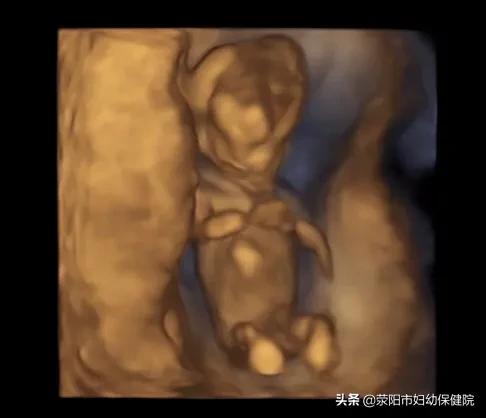

3.大排畸:

也就是在22-24周要做的四维彩超。这段时间胎儿大小和羊水适中,是筛查胎儿畸形的最好时期,孕妇们不要忽略,可以合理安排时间,赶在24周之前去做。